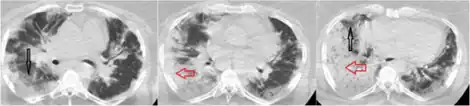

| a-f) Chest computed tomography and histologic findings of viral pneumonia | |